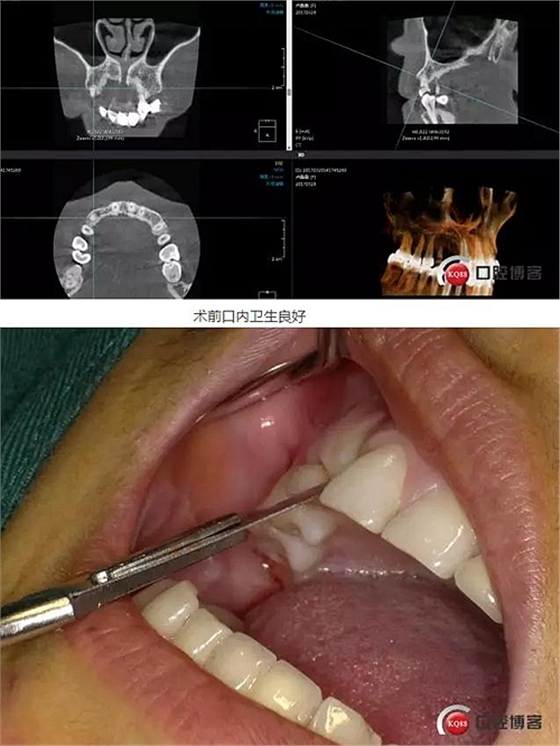

患者右上二缺失,CT示唇腭向骨量不足,右上3為乳牙滯留且骨量足設(shè)計(jì)右上三即拔即種手術(shù)

術(shù)前ct